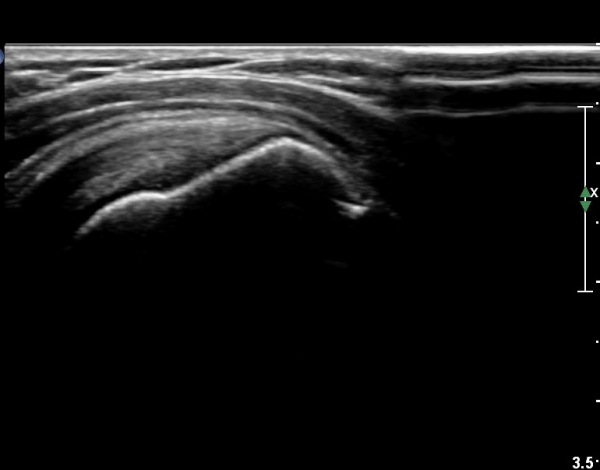

°ß°©ÇϱٰǠȾ´Ü¸é°Ë»ç¿¡¼­ ÇϺΠ°ß°©Çϱٰdz»  ÀÛÀº ¼®È¸È­ µ¢¾î¸®°¡ °üÂûµÈ´Ù(»çÁø 5).